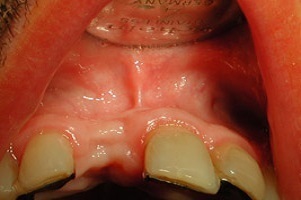

- Cas 2:

Dans une volonté de discrétion et de naturel, le patient a demandé que la couronne sur implant soit aussi jaune que la dent naturelle remplacée